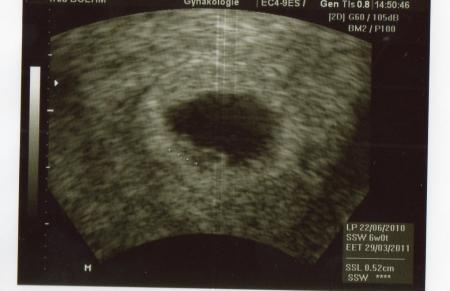

US Bilder 6+0 und 8+0

Hallo, ich versuche mal die Bilder einzustellen, vielleicht klappts... LG hier 6+0